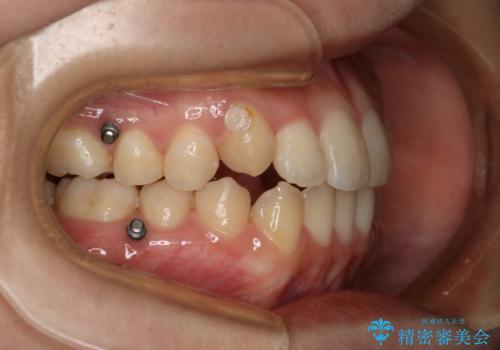

八重歯とクロスバイト:インビザライン治療

- 八重歯が気になるとの事でご相談にいらした方です。

インビザラインで綺麗に並べました。

気になっていた八重歯が綺麗になって大変喜んでいただけました。